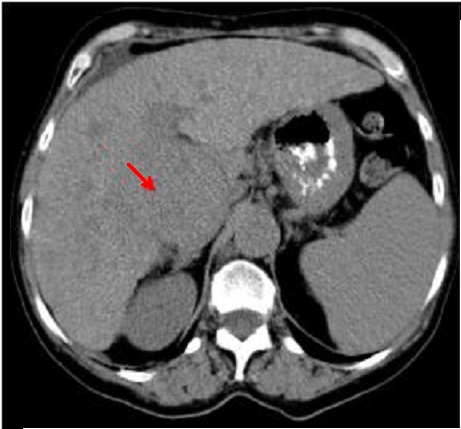

Aspect d'une masse a

hypodense du carcinoma hepatocellulaire du foie

droit ( fleche rouge ) . Image radiologique TDM en

coupe axiale en phase non injecte |